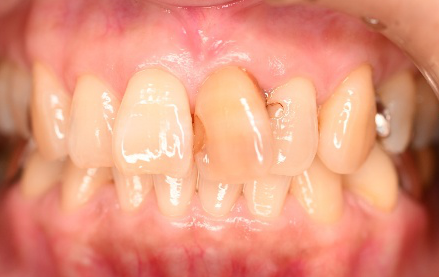

女性 Mさん 50代 (オールセラミック冠)

主訴

上の前歯をきれいにしたい。

治療内容

前歯3本にオールセラミック冠を被せて、歯並び及びすり減った歯を審美的に回復しました。歯ぎしりが強くあることがわかりましたので、マウスピースを使ってもらう事にしました。

所感

一番オススメな方法は、矯正をし、歯並びを整えた後、すり減って形が変わってしまった歯に被せ物をすることをお話ししました。患者さんは、3本に被せ物をすることにより歯並びをきれいにすることを希望されました。

治療後、「曲った前歯が長年コンプレックスでした。セラミックの歯の色合いや形が自然な仕上がりで、相談して本当に良かったです!神経を抜くこともなく治療ができ、予定よりも低料金にしてもらえたのがありがたかった。先生も、歯科衛生士さんも事務の人も皆、優しく寄り添った対応をしてくれました。ありがとうございました!」と、とても嬉しいお話しをしてくださいました。

オールセラミック冠3本:¥93,500(生活歯)×3本=¥280,500(税込)

Before

After